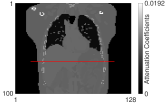

We used the XCAT [44] phantom (Fig. 2) to simulate Y-90 PET following radioembolization. We set the image size to 128128100 with a voxel size 4.04.04.0 (mm3) and chose 100 slices ranging from lung to liver. To simulate extremely low count scans with high random fractions, typical for Y-90 PET, we set total true coincidences and random fractions based on numbers from patient PET imaging performed after radioembolization [45]. To test the generalization capability of the trained BCD-Net, we changed all imaging factors between training and testing dataset. Here, imaging factors include activity distribution (shape and size of tumor and liver background, concentration ratio between hot and warm region) and count-level (total true coincidences and random fraction). Fig. 2 and Table I provide details on how we changed the testing dataset from the training dataset. We trained BCD-Net using five pairs () of 3D true images and estimated images at each iteration (1 true image, 5 realizations). We generated multiple (5) realizations to train the denoising NN to deal with the Poisson noise. We also generated 5 realizations (1 true image, 5 realizations) as a testing dataset to evaluate the noise across realizations.

II-F Evaluation metrics

For the XCAT phantom simulation, we evaluated each reconstruction with contrast recovery (CR) (volume-of-interest (VOI): cold spot indicated in Fig. 2), noise across realizations, root mean squared error (RMSE), and contrast to noise ratio (CNR). For the physical phantom measurement, we used CR (VOI: hot spheres) and CNR averaged over multiple hot spheres. We define each VOI’s mask based on attenuation map interpolated to PET voxel size. For the patient measurement, we used CNR and the field of view (FOV) activity bias since the total activity in FOV is known (equal to the injected activity because the microspheres are trapped) wheareas the activity distribution is unknown:

where is mean counts in the VOI, is true ratio between hot and warm region, denotes the th voxel of an image , is the number of realizations ( in both XCAT phantom simulation and physical phantom measurement) and is the number of voxels in the volume of liver, is standard deviation between voxel values in uniform background liver (indicated in Fig. 2), and is the total number of voxels in the FOV. As the background region when calculating the patient CNR, we used a part of liver region that has relatively uniform activity distribution.

| Attenuation map (coronal) | Attenuation map (axial) | True activity (training) | True activity (testing) | Zoomed in |

|---|---|---|---|---|

![]() |